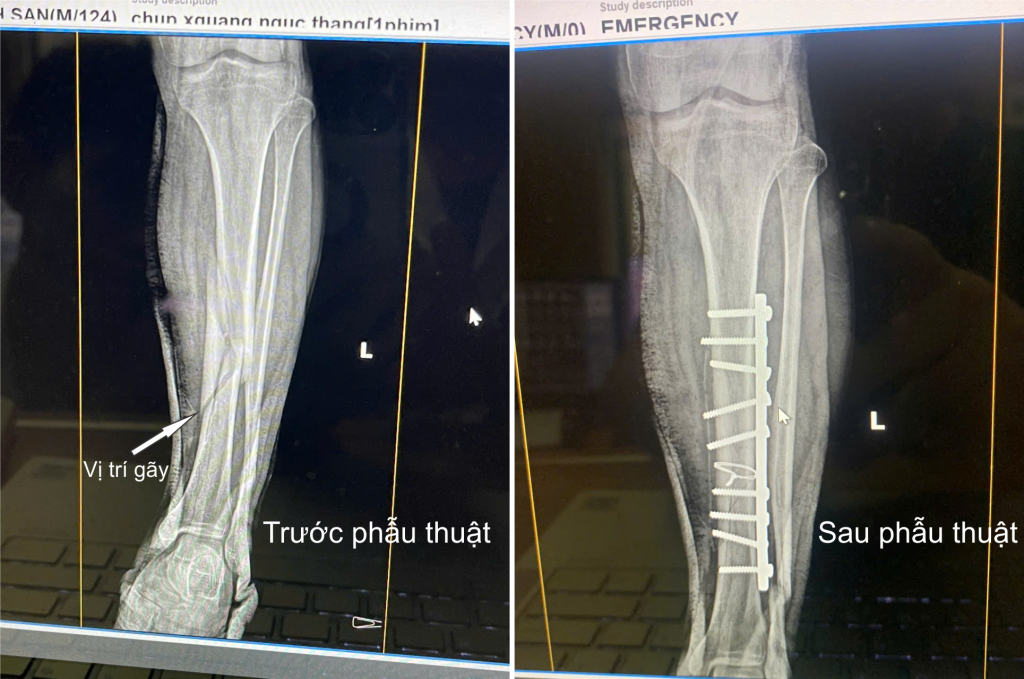

Ngày 15/10/2024, Trung tâm Y tế huyện Yên Lập tiến hành phẫu thuật kết hợp xương chày trái bằng nẹp vít cho người bệnh S, 39 tuổi. Trước đó, vào chiều ngày 14/10/2024, anh H.M.S, 39 tuổi, ở thôn Đắng, xã Thượng Long, huyện Yên Lập, tỉnh Phú Thọ trong lúc lao động đã không […]